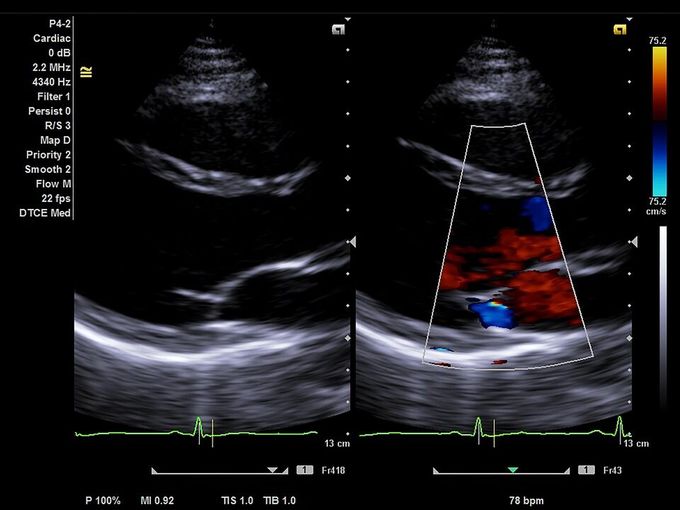

Кроме новой техники, можно заказать восстановленные медицинские системы: ультразвуковые сканеры, томографы, флюороскопы, ангиографы и хирургические установки С-дуга.